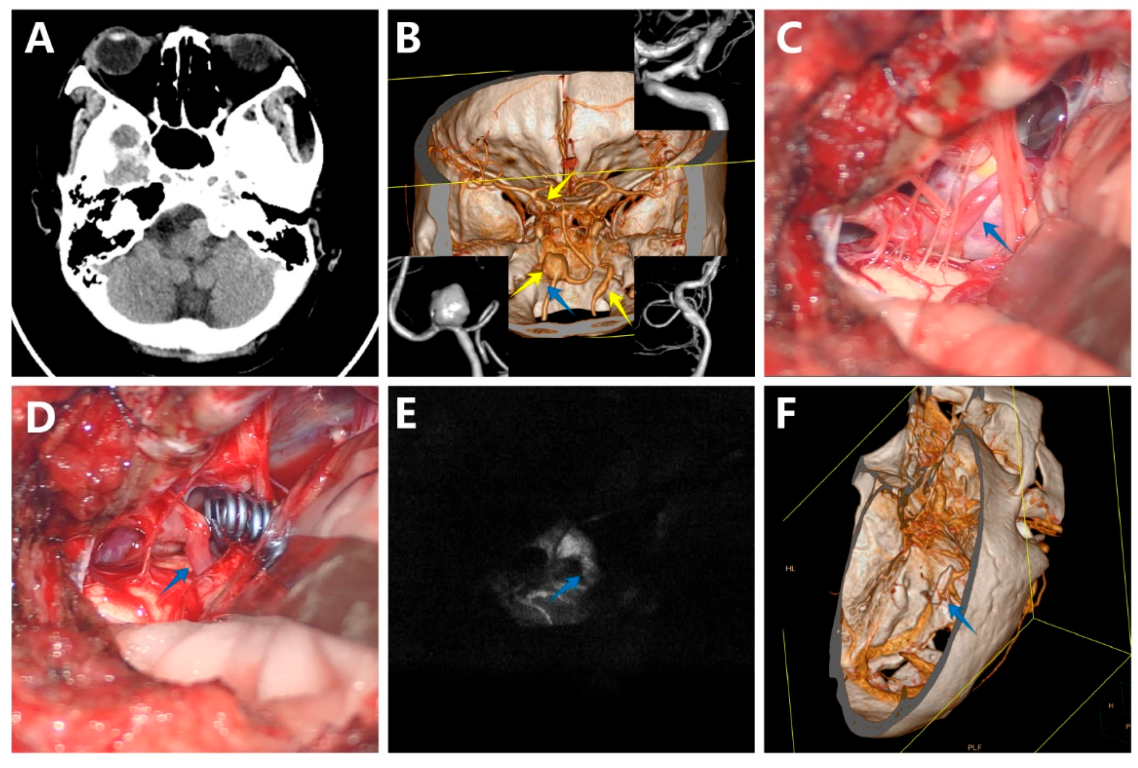

3.5.1. Case 1